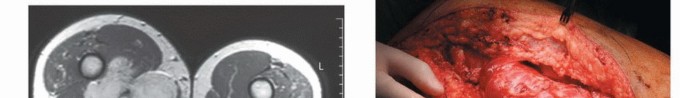

في عقود مضت، كان التعامل مع الأورام الكبيرة أو المعقدة في هذه المنطقة غالبًا ما ينتهي بالبتر، مما كان يترك أثرًا نفسيًا ووظيفيًا عميقًا على حياة المريض. لكن بفضل التطورات المتسارعة في عالم الطب والجراحة، لم يعد البتر هو الخيار الوحيد. لقد شهدت التقنيات الجراحية تطورًا مذهلاً، مدعومة بتقدم هائل في التشخيص التصويري والعلاجات المساعدة مثل العلاج الكيميائي والإشعاعي، مما فتح آفاقًا جديدة أمام الحفاظ على الطرف المصاب. أصبح الهدف الأسمى هو استئصال الورم بالكامل مع الحفاظ على أكبر قدر ممكن من وظيفة الطرف، مع تقليل معدلات تكرار الورم وتحسين جودة حياة المريض بشكل جذري.

في قلب اليمن، وتحديدًا في صنعاء، يقف الأستاذ الدكتور محمد هطيف كعلم بارز في هذا المجال. بصفته أستاذًا في جامعة صنعاء واستشاريًا لجراحة العظام والأورام بخبرة تتجاوز 20 عامًا، يُعد الدكتور هطيف مرجعًا طبيًا لا يضاهى. لقد كرس حياته لتقديم أحدث وأدق التقنيات الجراحية، بما في ذلك المايكروسيرجري (الجراحة المجهرية) التي تتيح له التعامل مع أدق الأوعية والأعصاب، والمناظير الجراحية بتقنية 4K للحصول على رؤية فائقة الوضوح، بالإضافة إلى خبرته العميقة في جراحات استبدال المفاصل (Arthroplasty) التي قد تكون جزءًا من خطة إعادة الإعمار المعقدة. يلتزم الدكتور هطيف بأعلى معايير النزاهة الطبية والمصداقية، ويضع مصلحة المريض في المقام الأول، مقدمًا حلولًا علاجية شاملة ومخصصة تضمن أفضل النتائج الجراحية والوظيفية.

- العلاج: يتضمن عادةً الجراحة (الاستئصال الواسع مع الحفاظ على الطرف)، وغالبًا ما يتبعها علاج إشعاعي أو كيميائي لتقليل خطر التكرار أو انتشار الورم.